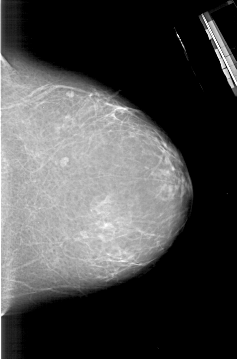

A_1830_1.RIGHT_MLO

RIGHT_MLO LINES 5836 PIXELS_PER_LINE 3631 BITS_PER_PIXEL 12 RESOLUTION 43.5 NON_OVERLAY